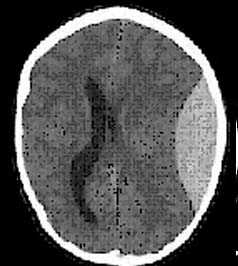

2. Диффузное аксональное повреждение. Диффузное аксональное повреждение (ДАП, синоним — диффузное повреждение белового вещества по механизму сдвига) возникает в результате приложения тяжелой деформирующей силы сдвига во время высокоскоростной травмы. Пациенты находятся в глубокой коме со стволовыми симптомами. Большинство повреждений происходит по средней линии с формированием небольших повреждений в глубоких слоях белого вещества больших полушарий, мозолистом теле и стволе головного мозга. В некоторых случаях выявляется небольшой осадок крови в одном из боковых желудочков, что вызвано разрывом его эпендимы. Полный объем повреждения можно оценить только на МРТ.

2. Диффузный супратенториальный отек мозга. Диффузный супратенториальный отек мозга может довольно часто встречаться при тяжелых травмах, особенно у молодых пациентов. Исчезновение контуров борозд мозга, сдавление сильвиевой щели и третьего желудочка, а также исчезновение базальных цистерн указывают на повышенное внутричерепное давление. Вся супратенториальная часть выглядит гиподенсной по сравнению с наметом и полушариями мозжечка. Контрастность между белым и серым веществом, как правило, теряется. Эти результаты могут быть обусловлены диффузной травмой, гипоксией или их комбинацией.

б - Острая окклюзионная гидроцефалия у маленького ребенка. Это осложнение развилось в течение 6 часов после первой КТ.